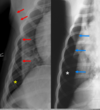

In right lateral:

the diaphragmatic crura are parallel (in left, they form a V)

in right lateral, the caudal vena cava merges with the cranially positioned crus and with the caudal when its left lateral

left lung is seen better in right lateral

heart more egg-shaped in right lateral, rounder in left.

In left lateral: blood vessels of cranial lobes are easier to differentiate.

thoracic lymph nodes may be seen in right lateral but rarely ever in left lateral.

Same animal in both pics.

● Expiration

– Cardiac silhouette appears larger

– Cranial and caudal margin less

defined